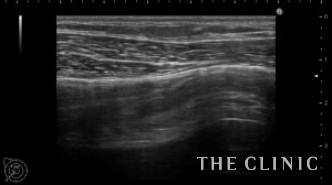

比較のためヒアルロン酸が入っていない部位をまずはご覧ください。